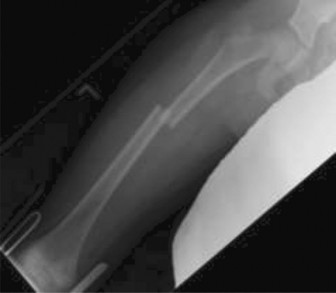

CASE 8 A 7-year-old girl is transferred to the ER after suffering an injury playing tackle football with her older brothers. She has notable deformity of the right thigh and was in significant pain. She was placed in a traction splint at the outside hospital and sent with the following x-ray (Fig. 10–10).

Figure 10–10

You call for a portable x-ray (Fig. 10–11) to assess her alignment in traction while you obtain a full history from the family. They report that she is otherwise healthy and a very active “tomboy.” The nursing staff attempts to weigh her in the bed as part of her assessment and the weight is 35 kg. You find her to be hemodynamically stable on examination. She has no abdominal tenderness and the

other extremities have full, painless ROM of every joint and no tenderness or swelling. Her distal motor and sensory examination is intact in the injured leg.

Figure 10–11